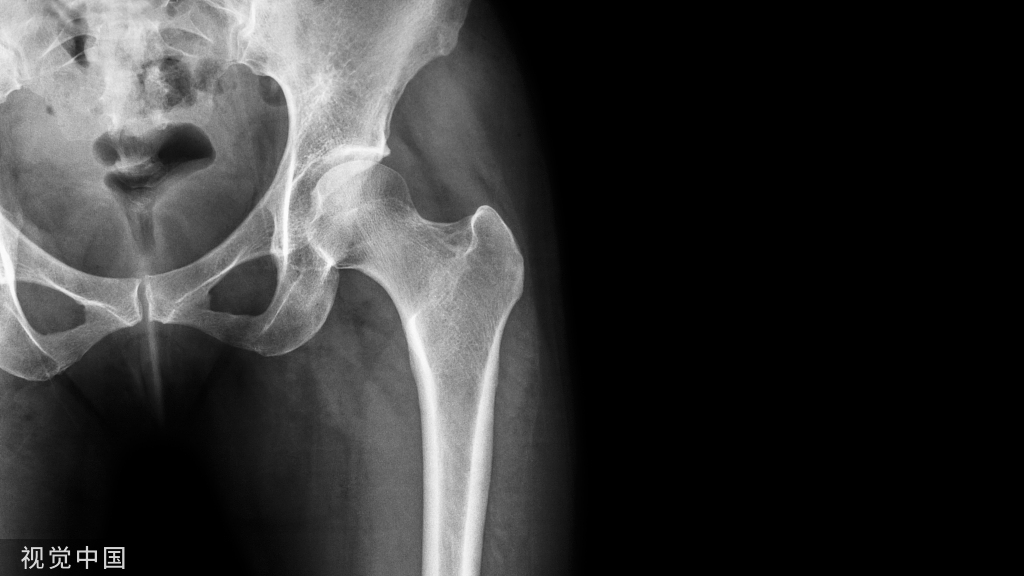

首先,在泪滴的水平线上画一条水平线。肢体长度从这条水平线测量到双侧小粗隆中心的水平。在小粗隆上选择了一个两侧看起来相等的位置。测量从颈部切口水平到坐骨的偏移量

测量肢体长度和偏移量的步骤。首先,使用以下标准获得中性旋转的骨盆前后(AP)片是必要的:骶骨中心应与耻骨联合中心对齐,骨盆倾斜度不应与患者的站立AP片有显著差异。两个股骨应该处于类似的小粗隆侧貌所示的相同的旋转度。两条腿的外展程度应相当,且屈曲程度相同。